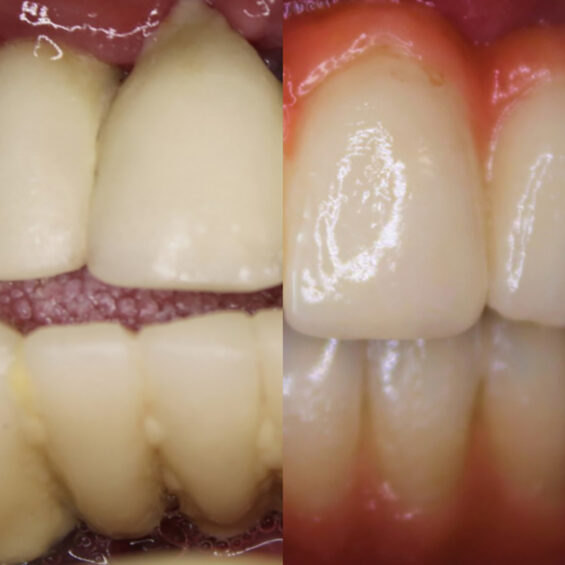

Decidí acudir ya que no aguantaba el dolor que tenía, no podía comer y me afectaba en el día a día. Cuando Susana me exploró, inmediatamente supo lo que necesitaba. Los dientes que me quedaban no podían aguantar más tratamientos Planificó la extracción de todos ellos y el tratamiento de All On Four superior y 6 implantes mandibulares . Con colocación inmediata de dientes el mismo día que me los extrajo y colocó los implantes. Entrar y salir con dientes.

Valentín ha sido en todo momento un paciente comprensivo y colaborador. Su cirugía requirió una planificación muy precisa, pues se trataba de implantes postextracción y carga inmediata. Finalmente, una rehabilitación fija sobre implantes con todos los criterios que exigía.

- Rehabilitación completa sobre implantes